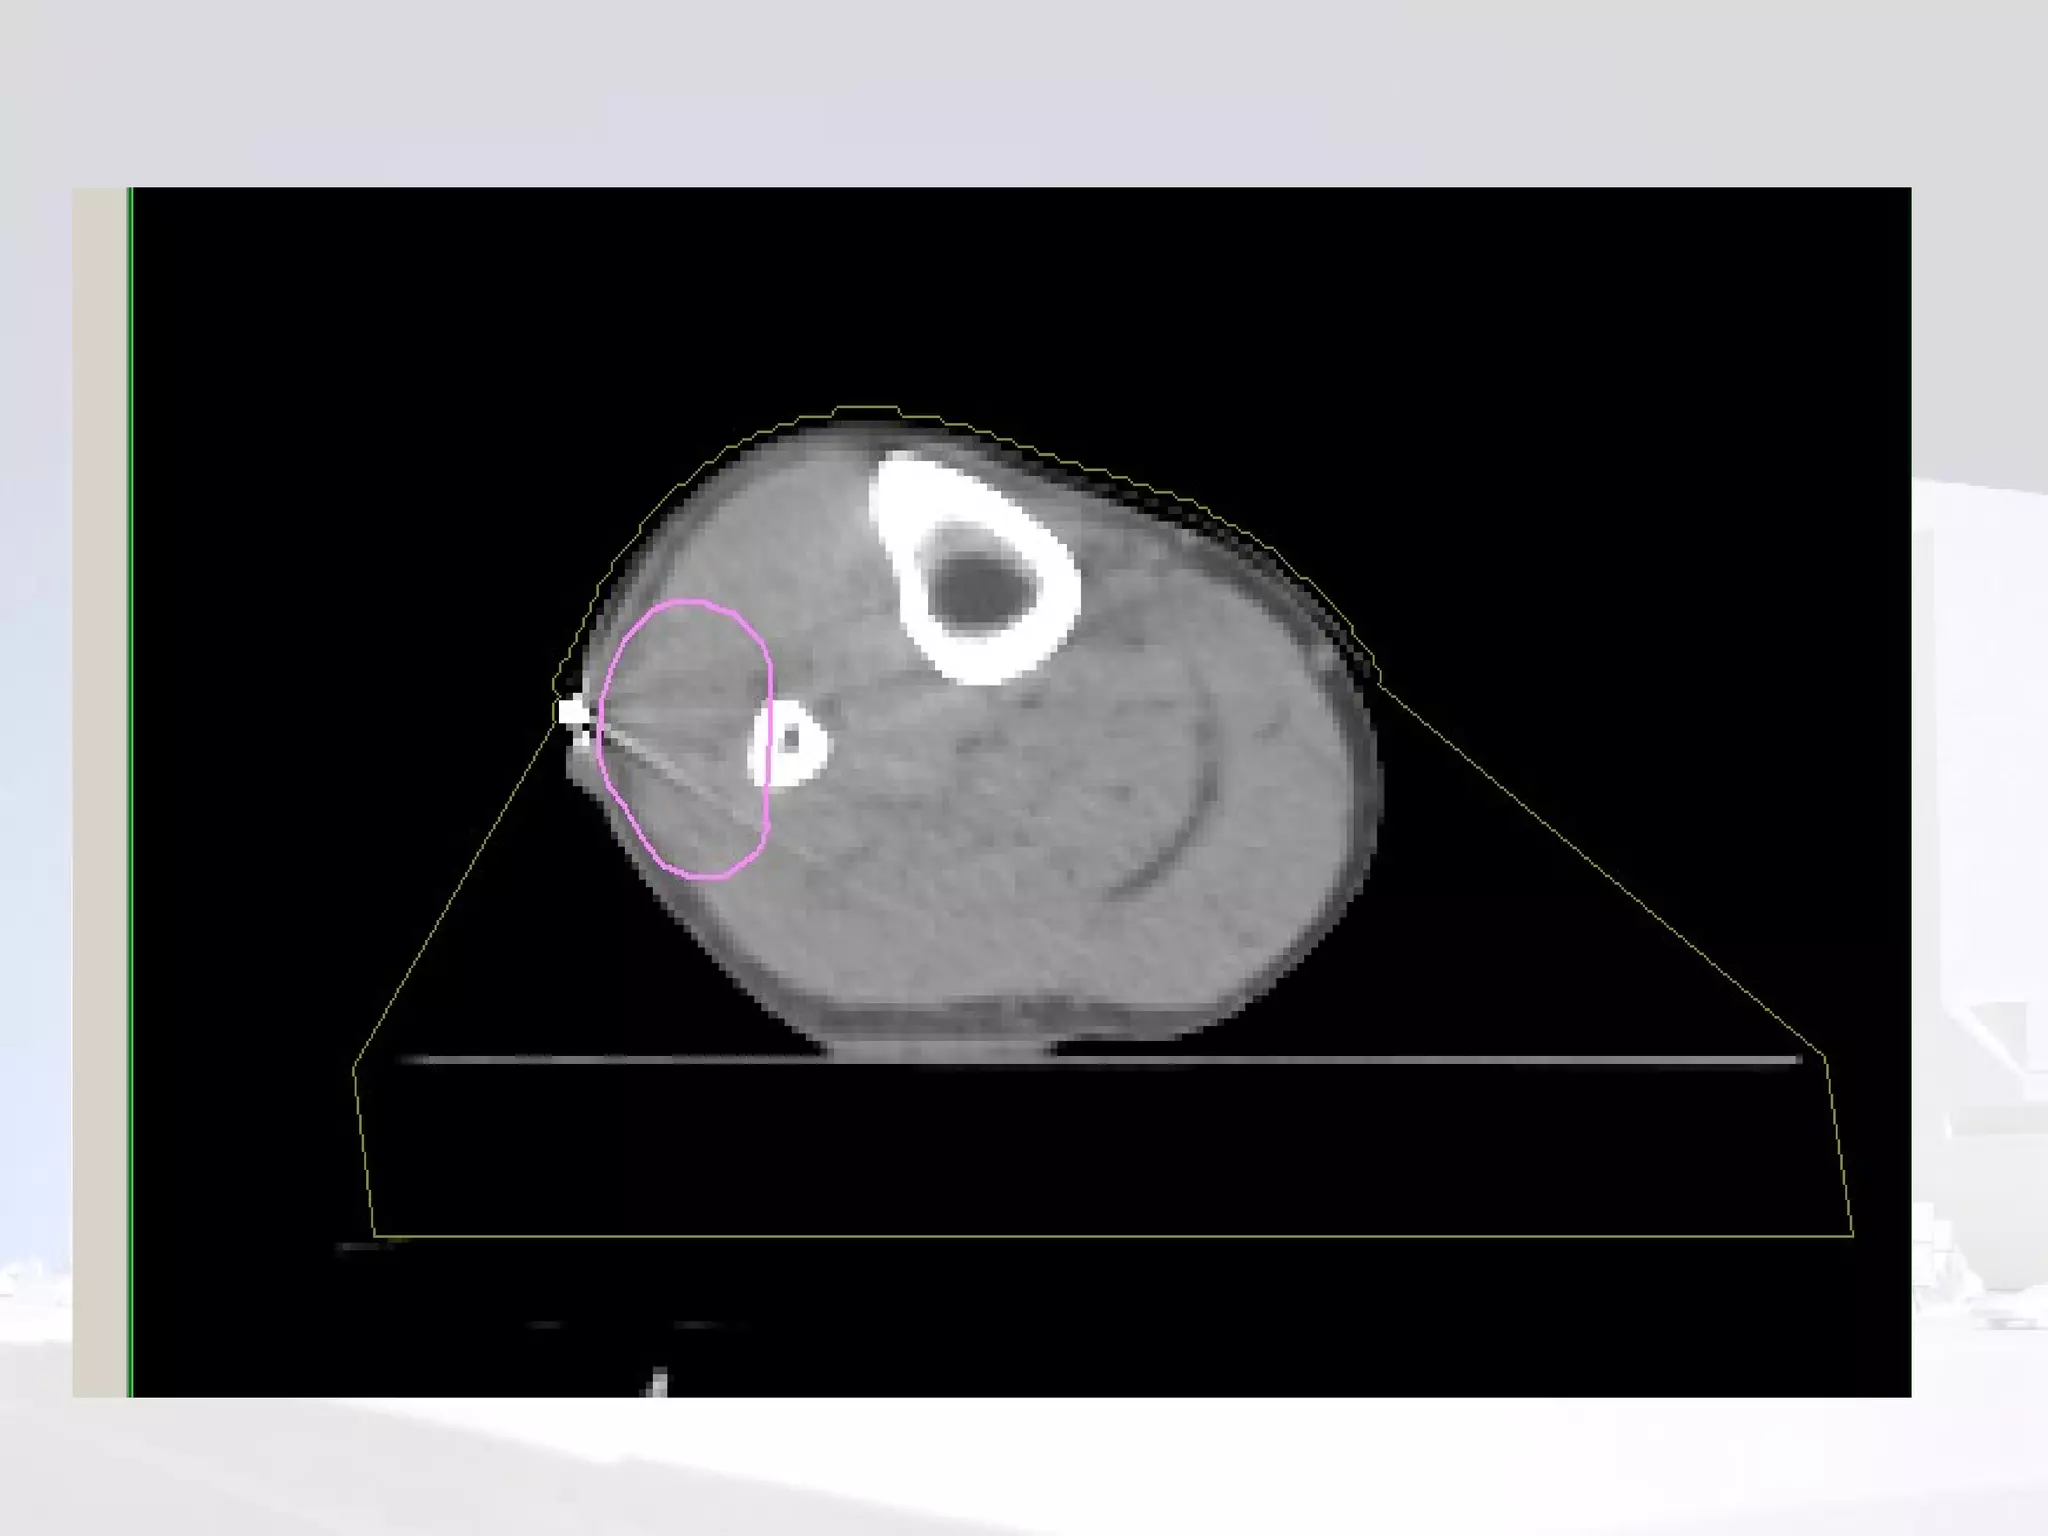

Planning

Phase I  Volume definition GTV  reconstructed from pre-op imaging. Consider compartment at risk of microscopic spread. Should include biopsy site and scar CTV  (length) =  GTV  + 4-9cm (usually ~5cm) PTV  =  CTV  + 5-10mm (depending on departmental set up) or 1 cm beyond scar  Trans-axial CTV -  treat width of compartment or  GTV  + 2-3cm

Sparing a “corridor” Leaving an area of normal tissue within the circumference of the limb can reduce risk of lymphoedema

Sparing a “corridor ” Leaving an area of normal tissue within the circumference of the limb can reduce risk of lymphoedema